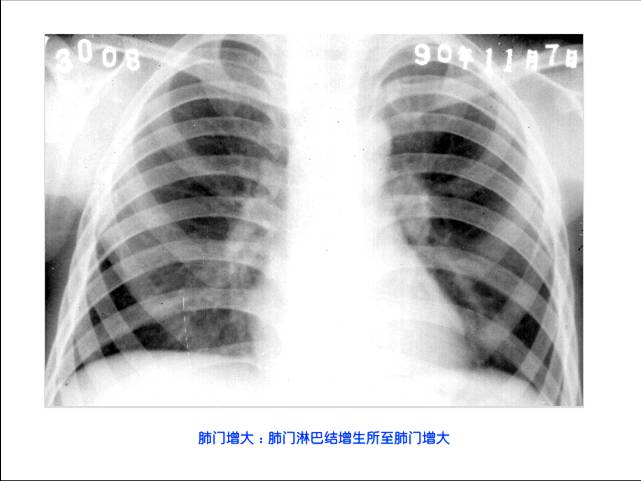

照片名称:肺门增大